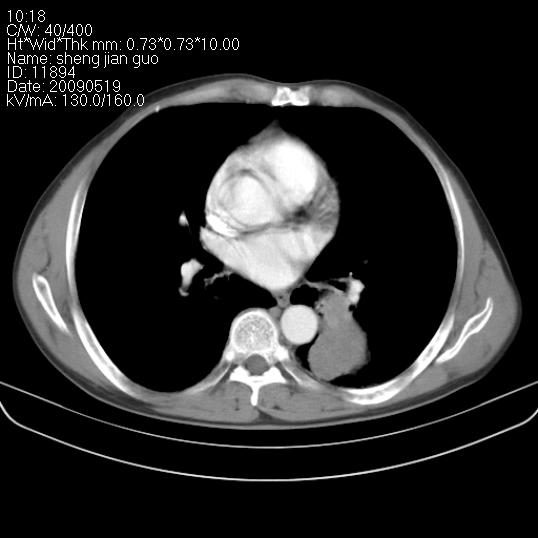

以下是引用zjzjr在2009-5-19 17:25:00的发言:[br]支持楼主考虑,另左肺下叶阻塞性炎症。

以下是引用zhao_bin2008在2009-5-19 17:48:00的发言:[br]支持左肺下叶周围型肺癌并阻塞性肺炎。

以下是引用zsl6918在2009-5-20 7:10:00的发言:[br]左侧中心型肺癌!